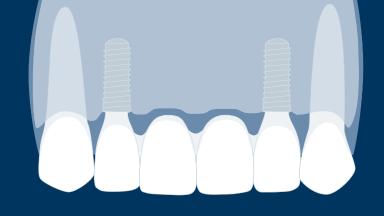

O clínico que pratica implantodontia é confrontado com diferentes situações clínicas, que variam de um único dente ausente, a um espaço edêntulo com vários dentes ausentes até completar rebordos totalmente edêntulos. Uma vez estabelecido um plano de tratamento completo, diferentes desenhos de configurações podem ser possíveis para próteses implantossuportadas. Cada desenho da prótese tem suas vantagens e desvantagens. O desenho da prótese deve basear-se na condição clínica para garantir que o número apropriado de implantes seja instalado nas posições protéticas corretas usando implantes com dimensões apropriadas.

- espaços edêntulos curtos

- espaços edêntulos extensos